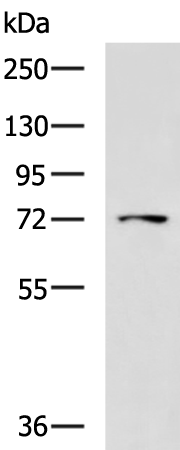

分类: 科研抗体货号: P00178别名: LFTD; NBIA3应用: WB,IHC反应种属: Human